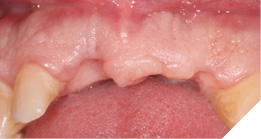

The existing metal ceramic bridgework was thick and bulky, but the patient was used to it. The patient also didn’t have any pain or discomfort yet from the slightly loose bridge or dental caries. The patient was most concerned the bridge would suddenly come out and would have a space (Figs. 3-4).

Fig. 3

Fig. 4